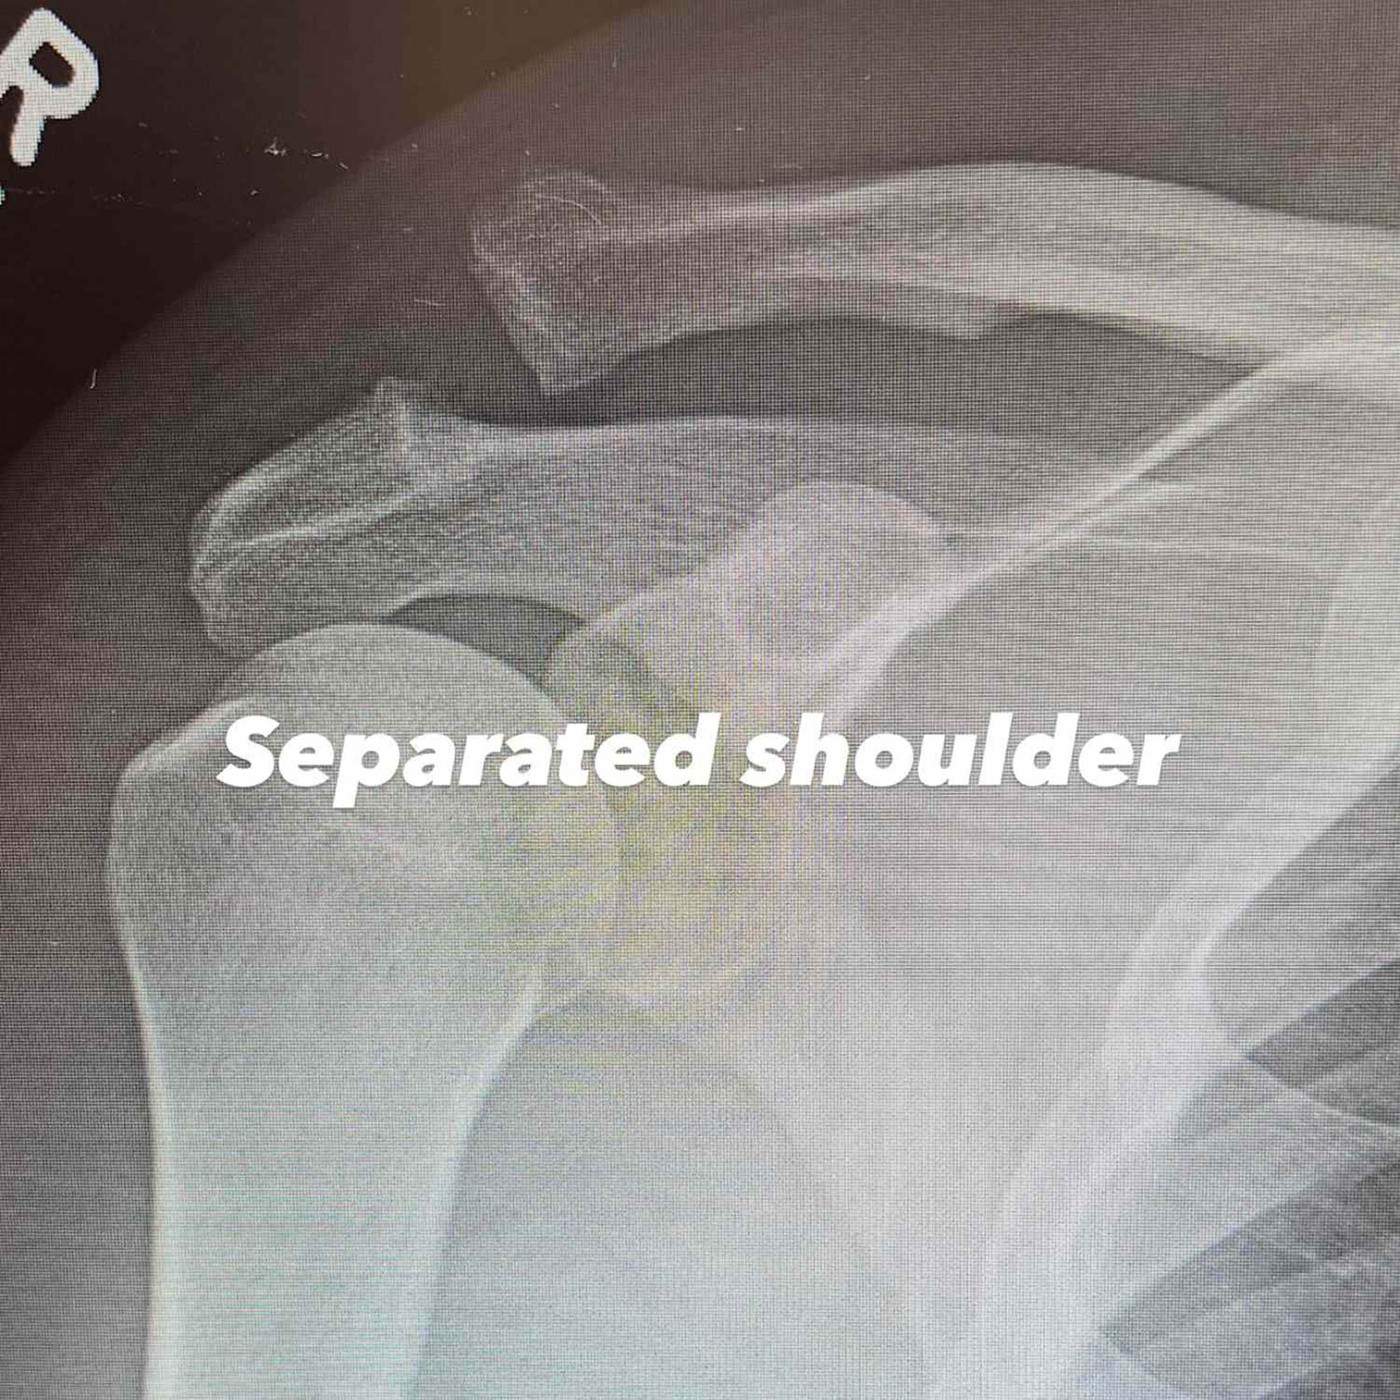

Channing Tatum s-a accidentat la umăr.

Un actor celebru a ajuns pe patul de spital! Este nevoit să se opereze de urgență: ”Va fi greu” Un actor celebru a ajuns pe patul de spital! Este nevoit să se opereze de urgență: ”Va fi greu” Un actor celebru a ajuns pe patul de spital! Este nevoit să se opereze de urgență: ”Va fi greu”